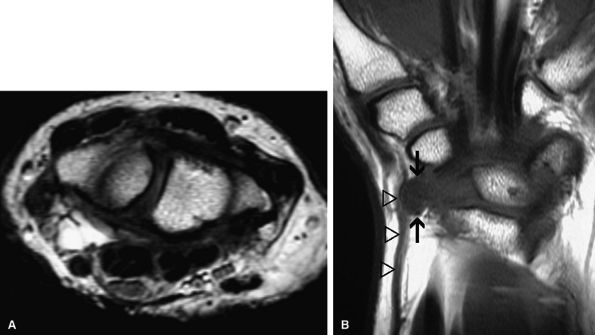

FIGURE 12.49 ● Ganglion cyst compressing the ulnar nerve. Axial (A) and oblique coronal (B) fat-suppressed T2-weighted images demonstrate a ganglion cyst (arrows) within Guyon's canal.

FIGURE 12.50 ● Ganglion cyst compressing the superficial radial nerve. Axial fast spin-echo T2-weighted image (A) and coronal T1-weighted image (B) show a bilobed ganglion cyst (arrows) compressing the superficial radial nerve and radial artery (arrowheads).